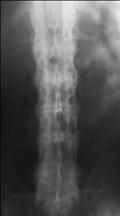

К числу поздних изменений относят синдесмофиты: линейные зоны оссификации наружных частей фиброзных дисков, в основном не выходящие за контур тел позвонков (первые синдесмофиты обычно появляются на границе поясничного и грудного отделов), окостенение межостистых и жёлтых связок, атакже анкилоз дугоотростчатых суставов с оссификацией их капсул. Распространённая оссификация указанных структур создаёт карти­ну «бамбуковой палки» (рис.6-7).

Рис. 6-7. «Бамбуковый» позвоночник.